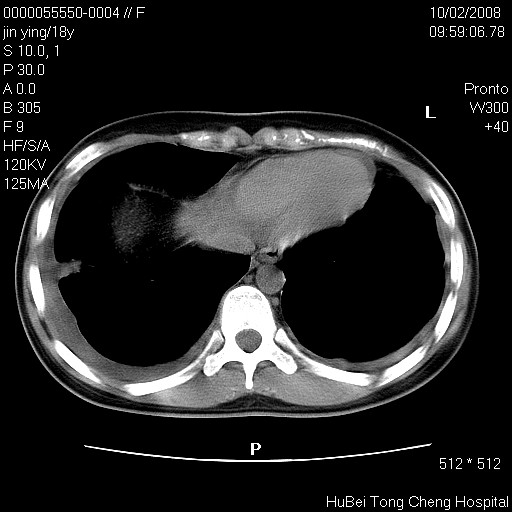

患者 女,18y。发热十余天,伴咳嗽。pe:t39⒈℃,bp 110/80mmhg,p 86次/min。神清,精神欠佳。双肺可闻及少许湿罗音。既往史不详。

临床诊断:肺部感染?

胸部ct轴位平扫(层厚10mm,螺距1.5,重建间隔10mm),图像如下: